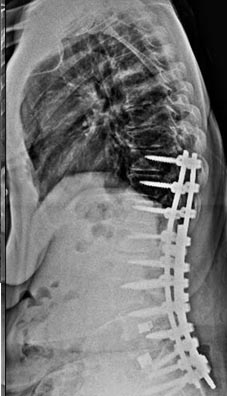

21 year old woman with very ridged 90 degree Scheuremann's kyphosis corrected to 40 degrees.